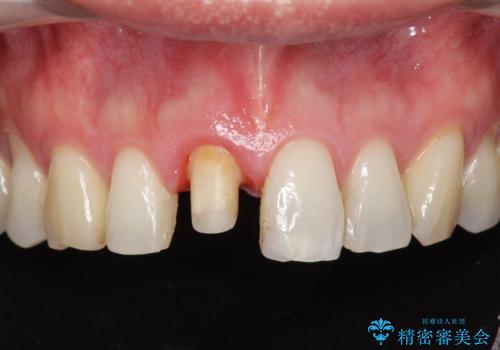

- 前歯の変色が気になり審美障害の改善を求めて来院されました。

根管治療に伴う歯の色調変化はよく見られる所見です。

セラミッククラウン製作を行い審美性の改善を計画します。

- 15.4万円(仮歯・ファイバーコア・ジルコニアクラウン)費用は治療当時の料金となります